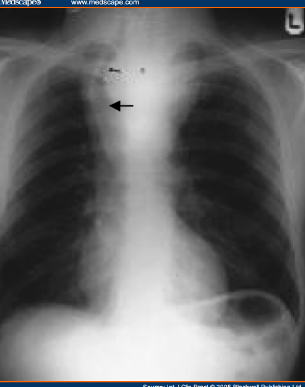

次の写真の矢印部分に黒い線が見え、縦隔気腫が認められる。

縦隔気腫があるかないか

縦隔気腫とは激しい咳などにより胸腔内圧が高くなり、気管支から縦隔に空気が入りこんだ状態。喘息重責発作、間質性肺炎、人工呼吸なども原因となる。